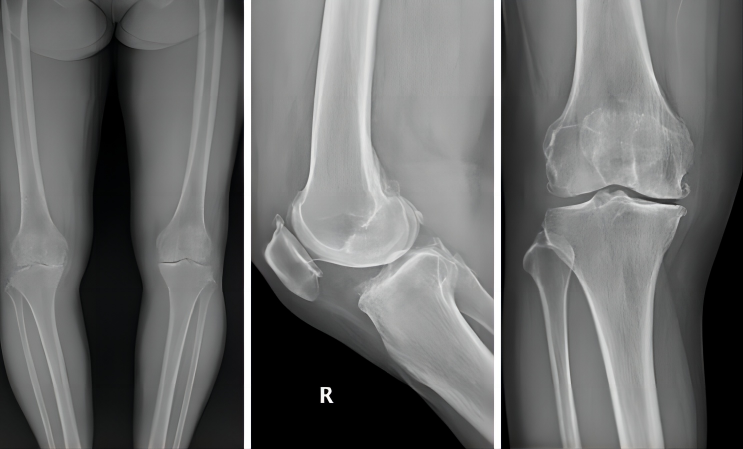

60岁的陈女士(化名)右膝关节疼痛已有3年,最近六个月疼痛加重,日常屈伸活动受限,走路跛行,影响与孙儿互动,自主家务等日常生活。

因为长期疼痛且疼痛加重影响日常生活,陈女士和家人萌生了关节置换的想法。在得知广州和睦家医院引入了MAKO骨科手术机器人,就马上预约到骨科刘宁主任门诊就诊,经过医生的诊断,诊断为膝关节骨性关节炎,可以选择用MAKO机器人辅助完成单髁关节置换术,不止可以解除疼痛困扰,还能最大限度保留骨量,保留患者的本体感觉和关节功能。

MAKO机器人辅助单髁置换术所搭配的关节假体是史塞克公司MCK假体,该假体为全解剖型设计,更好的与人体骨骼形态相匹配。传统单髁置换手术已经具有微创、不损伤肌肉、保留骨量多、术后恢复快的优点,从这个病例中,MAKO机器人把这种优势进一步增加,并且更加精准,表现在以下几点:

单髁关节置换术的手术视野有限,与传统手术相比,单靠主治医生肉眼判断容易出现误差。而MAKO机器人可以帮助医生判断截骨的位置,使关节假体放置的位置更加准确,避免假体过大或过小,也可以避免假体周围骨折、软组织激惹等;